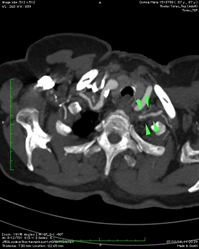

Blood tests revealed no changes, except an Erythrocyte sedimentation rate (ESR) of 56m, and C-reactive protein (CRP) of 44 mg/L. Plasma and urinary catecholamine levels were within the reference values. The autoimmunity study was negative. The electrocardiogram showed sinus rhythm, with a heart rate of 73 beats per minute, with no changes in rhythm, conduction, or ventricular repolarization. The 24-hour Holter confirmed the baseline sinus rhythm and some periods of 2nd-degree atrioventricular block Mobitz I during sleep. To complete de cardiac study, an echocardiogram was performed, which revealed mild mitral-aortic degenerative changes, aortic valve fibrosis, mitral ring calcification, mild regurgitation, and an enlarged left atrium. For the absence of palpable pulses, an Arterial Eco-Doppler of the Upper Limbs was performed, revealing a significant stenosis of the axillary arteries bilaterally, more severe on the right and with distal hemodynamic compromise. To exclude a Giant Cell Arteritis a Cerebral Vessel Wall MRI was performed and excluded changes in the temporal artery. Lastly, the Thoracic and Abdominal Angio-CT showed a diffuse thickening of the aorta wall, (Figure 1), stenosis of the left subclavian artery (Figure 2 & 3) with an inflammatory component, reduction in the caliber of the right subclavian artery and severe stenosis of the renal artery (Figure 4), thus suggesting a Takayasu Disease.

Figure 1 On axial Angio-CT slice, Diffuse thickening of the ascendent and descending aorta are indicated by green arrowheads and green line.

Figure 2 On axial Angio-CT slice, stenosis of the left subclavian artery with an inflammatory component is indicated by green arrows.